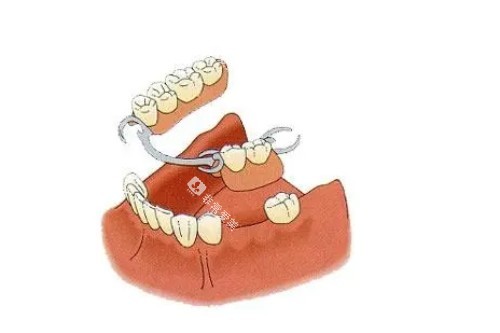

中端型吸附性义齿在材料和制作工艺上有所提升,能够更好地满足患者对舒适度和美观度的需求。其基托可能采用高性能塑料或金属支架,牙冠则可能使用更高品质的树脂或陶瓷材料。这种义齿的吸附力更强,佩戴起来更加舒适,且使用寿命更长。

材料:高性能塑料或金属支架,高品质树脂或陶瓷牙冠。

舒适度:佩戴舒适,吸附力强。

适用人群:追求性价比、对舒适度有一定要求的患者。